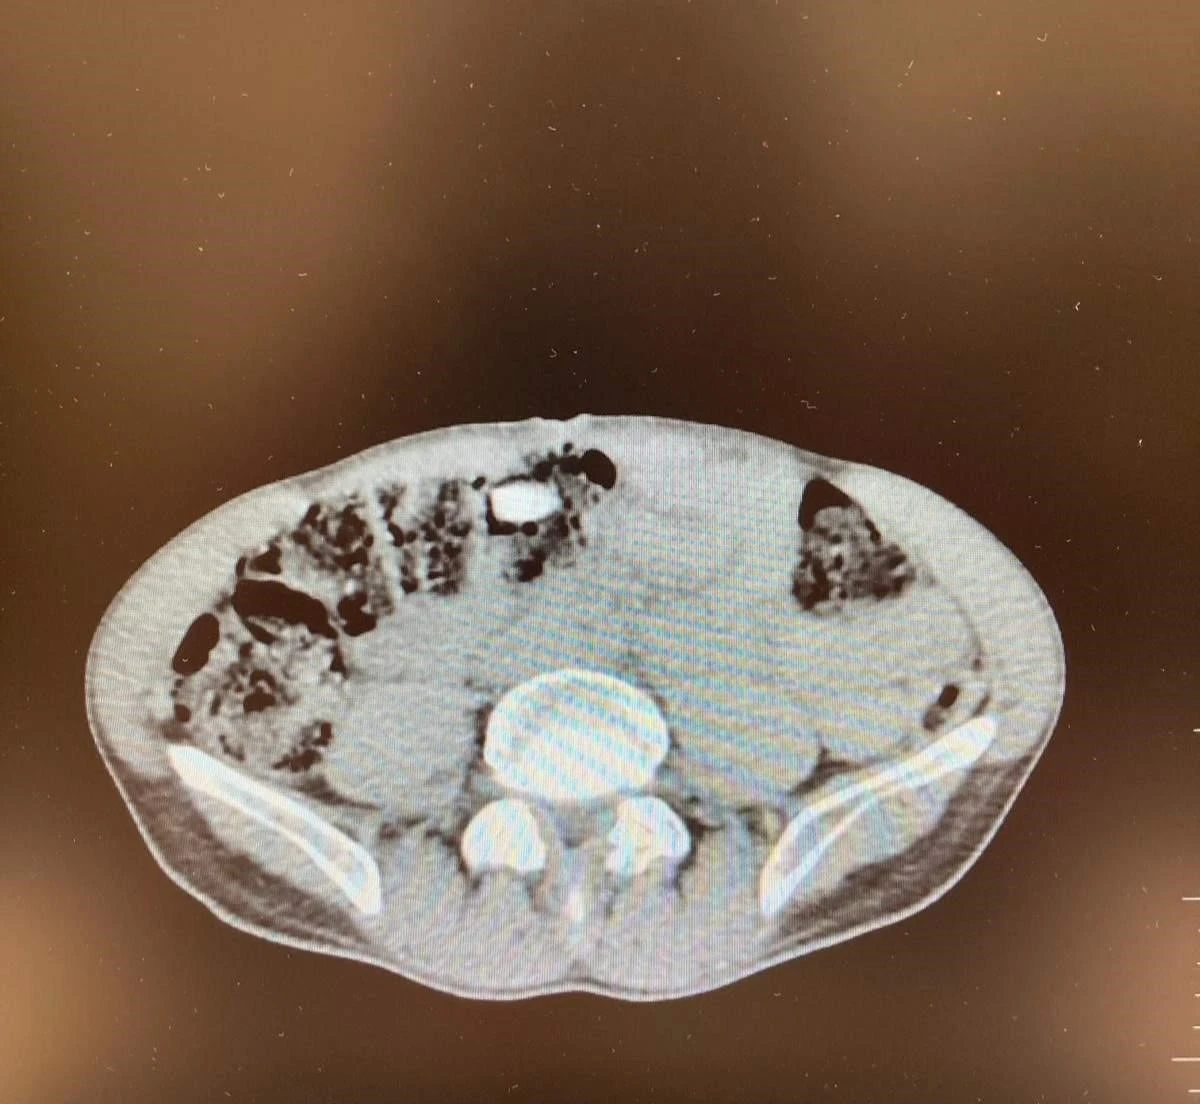

Denizli İl Emniyet Müdürlüğü Narkotik Suçlarla Mücadele Şube Müdürlüğünce uluslararası uyuşturucu madde ticaretinin önlenmesine yönelik çalışmalar devam ediyor. Yapılan incemeler ve değerlendirmeler sonucunda Denizli’ye havayoluyla yolculuk eden yabancı uyruklu şahsın uyuşturucu madde getireceği tespit edildi. Şüpheli, Narkotik Suçlarla Mücadele Şube Müdürlüğü ve Çardak Havalimanı Gümrük Muhafaza Bölge Amirliği görevlilerince müşterek yapılan çalışmalar neticesinde yakalandı. Şüphelinin eşyalarında yapılan aramalarda 6 parça halinde giysilere emdirilmiş şekilde 1 kilo 257 gram metamfetamin maddesi ele geçirildi. Yapılan iç beden muayenesinde ise 3 parça halinde 15 adet ecza hap ele geçirildi. "Uyuşturucu veya uyarıcı madde ticareti yapmak" suçundan adli makamlara sevk edilen şüpheli, tutuklanarak cezaevine gönderildi.